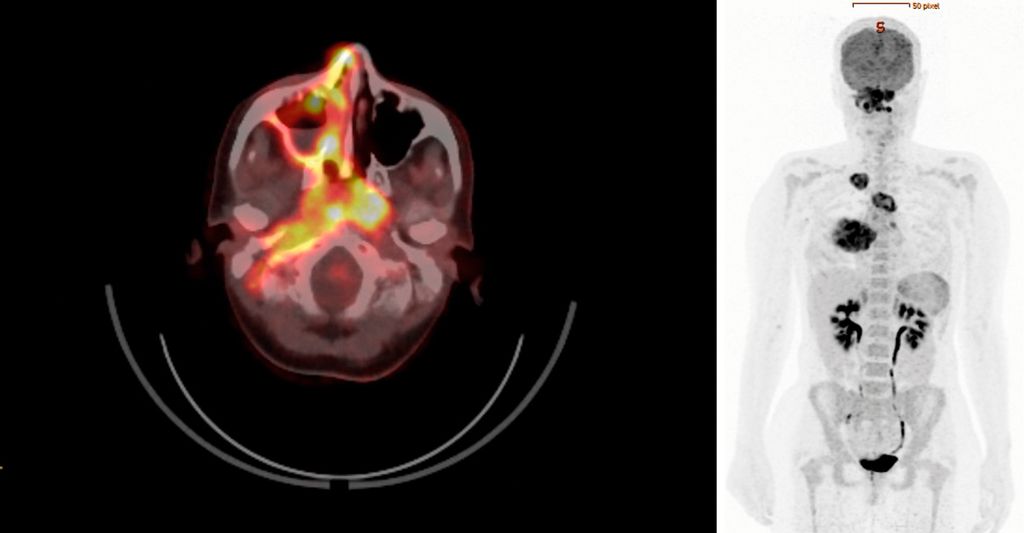

Zur weiteren Stadieneinteilung wurde ein 18F-FDG-PET/CT durchgeführt. Dieses wies eine hohe metabolische Aktivität auf – nicht nur in den pulmonalen Veränderungen, sondern auch im Bereich des raumfordernden Pseudotumors an der gesamten rechten Schädelbasis sowie in weiteren multifokalen Läsionen im Sinne eines generalisierten Stadiums mit Multiorganbefall (Abb.1).

Abb. 1: 18F-FDG-PET/CT mit hoher multifokaler metabolischer Aktivität bei Vaskulitis mit Multiorganbefall (Quelle: Universitätsklinik für Nuklearmedizin Innsbruck)